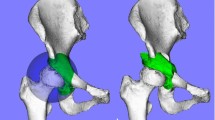

Bernese periacetabular osteotomy was first described in 1988 by Ganz et al. [1] and has been performed in Europe and North America. Its polygonal osteotomy design involves three cuts in the ilium, pubis, and ischial bones through a modified Smith-Petersen approach and maintains the integrity of the posterior column. RAO is a reorientational periacetabular osteotomy first described by Ninomiya and Tagawa in 1984 [2]. The surgical approaches and procedures of RAO have been modified, and it is currently widely used throughout Japan for patients with the early stages of osteoarthritis secondary to DDH. The design of the osteotomy is spherical, allowing the acetabular fragment to easily rotate and increasing the bone contact area between fragments for stability and bone healing (Fig. 12.1). RAO also maintains the integrity of the posterior column. CPO was modified from periacetabular osteotomy by Naito et al. [6]; the osteotomy design is spherical and performed through a modified Smith-Petersen approach.

(a) Design of rotational acetabular osteotomy and (b) position and alignment of a reoriented acetabulum were simulated three-dimensionally. Reprinted from [32]